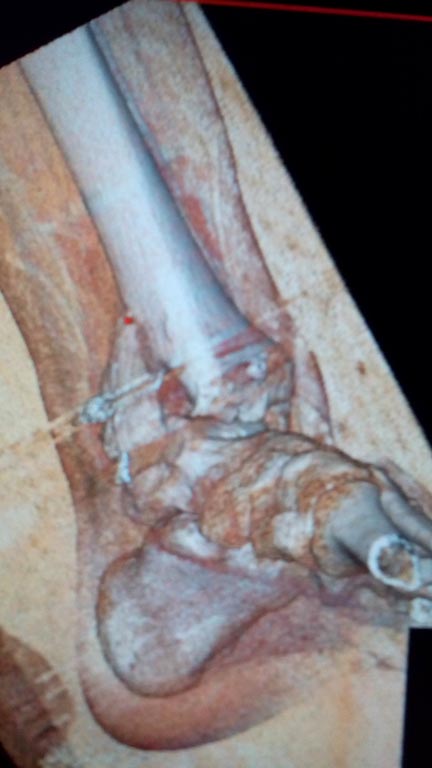

Мужчина, 1987 г.р. получил травму 10.2014. ДТП. Закрытый двухлодыжечный

перелом костей костей левой голени, перелом заднего края большеберцовой

кости с подвывихом стопы кзади, кнаружи. Наложен дистрактор.

Операция 10.2014: закрытая репозиция, остеосинтез спицами,

винтами. В дальнейшем произошло ожидаемое усугубление нарушений

взаимоотношений в голеностопном суставе.

"растоптана" латеральная суставная поверхность большеберцовой кости?